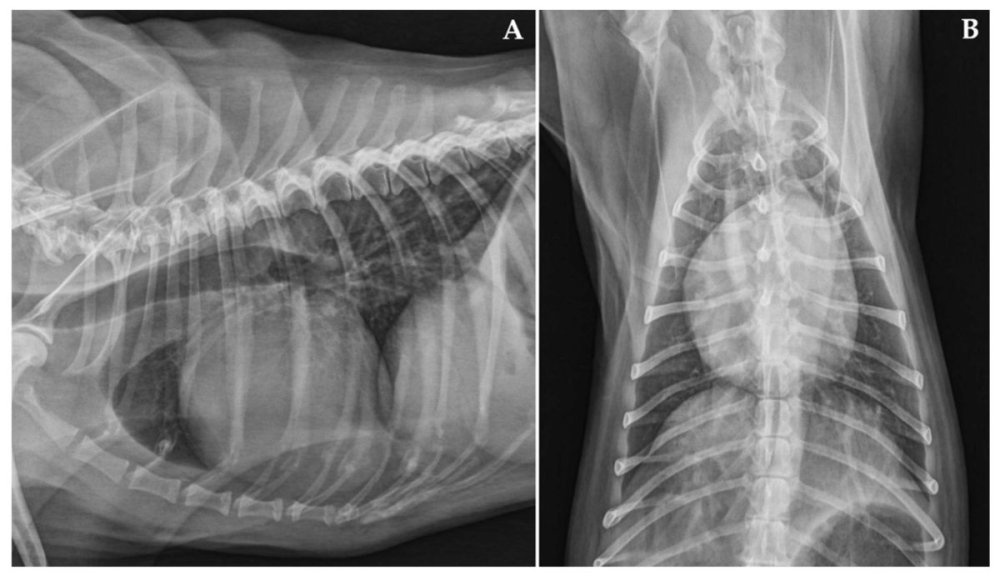

• Echocardiogram (heart ultrasound), this is the most definitive way to assess chamber size and pumping function for DCM.1

• Chest X-ray to check heart size and look for fluid in the lungs when heart failure is suspected.1